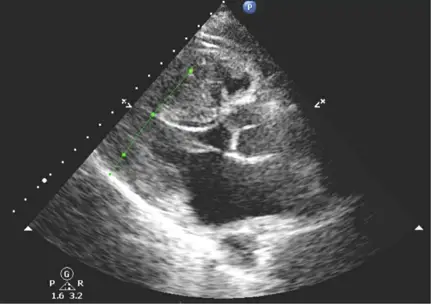

超音波影像

- 二維心臟超音波可見心室中膈明顯增厚,厚度可達 15 mm 以上,與後壁比例懸殊,呈非對稱肥厚。

- 左心室流出道區域見狹窄,可能伴隨收縮期前移的二尖瓣前瓣瓣膜 (SAM)

- 心尖與 LLSB 區域收縮期雜音 (grade 3/6),符合動態 LVOTO 臨床表徵。

以上 echo 所示即屬典型阻塞型 HCM 變異。